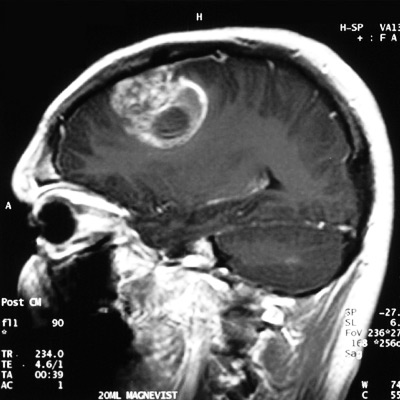

| Магнитно-резонансная томография (МРТ) | Получение детальных изображений структуры мозга для выявления врожденных аномалий, опухолей или последствий травм, которые могут быть причиной эпилепсии. |